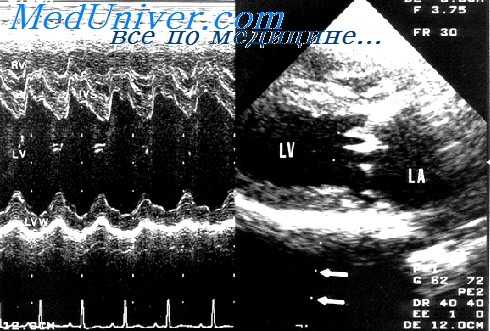

Объемная перегрузка желудочков сердца так же, как и систолическая имеет свои характерные признаки и ультразвуковые проявления. Изменения эхокардиограммы также, как и при систолической перегрузке аналогичны для правого и левого желудочков. Наиболее выраженным признаком при ультразвуковом исследовании является значительная дилатация соответствующего желудочка. Показатели размера желудочков сердца, осуществляющего объемную нагрузку, достоверно отличаются от аналогичных показателей при систолической перегрузке.

В отличие от группы пациентов с врожденными пороками сердца с систолической перегрузкой, толщина миокарда соответствующего желудочка не превышает верхней границы нормы.

Для объемной перегрузки желудочков сердца характерным является увеличение экскурсии стенок, ограничивающих желудочек. Для правого — это миокард его передней стенки и межжелудочковой перегородки; для левого — межжелудочковая перегородка и миокард задней стенки.